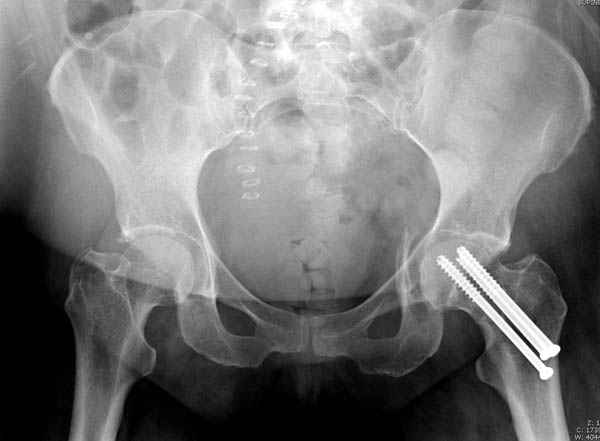

У нас в таких случаях однозначно сделали бы остеосинтез Ш.Б. компрессирующими винтами, затем ЗВО таза, однозначно с дополнительной фиксацией в этом же аппарате бедра с разгрузкой тазобедренного сустава

Фиксацию шейки провели когда получили окно, быстро

перкутанно смогли провести шурупы.

В положении на спине подвздошным и надлобковым доступом восстанавливается тазовое кольцо, фиксация пластинами. При хорошей репозиции может улучшиться конгруэнтность в суставе.

Затем, если положение хорошее, закрытый остеосинтез шейки винтами.

Если нет - в положении на боку, синтез задней колонны из наружно-латерального доступа и синтез головки винтами, но уже под визуальным контролем.

Применение аппарата нецелесообразно, т.к. репозиция такого повреждения в аппарате крайне сложна и скорее приведет к удержанию имеющегося неправильного положения, а это надо?

На картинке подобный случай, только без шейки, сделано через месяц или полтора после травмы.